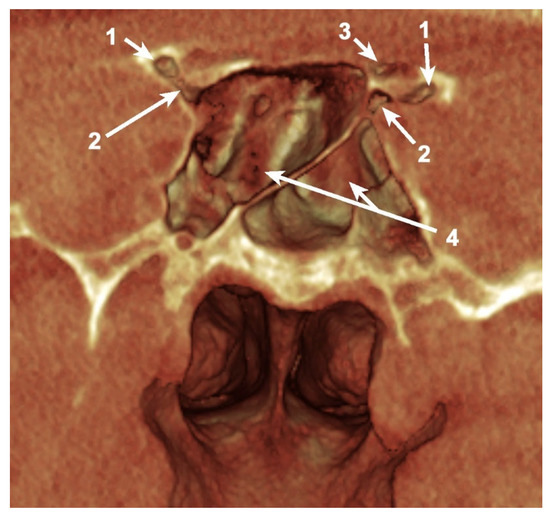

A total of 85 OS (53.12%) were pneumatized. The prevalence of OS pneumatization within the total was 67.5% (45 female and 9 male patients), 42.6% (23 cases) of them being unilateral (Table 1) (Figure 1 and Figure 2).

Figure 2. Coronal, bilateral three-dimensional volume rendering of the anterior clinoid process (ACP) and sphenoid sinus, posterior view. 1. Pneumatized ACP; 2. Pneumatized optic strut; 3. Pneumatized anterior root; 4. Sphenoid sinus.